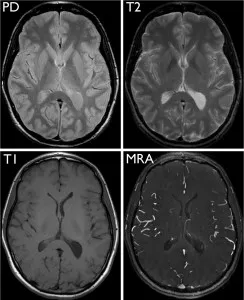

Selected images from a brain MRI obtained in a normal volunteer, all acquired at the same level through the head. Proton density (PD, top left), T1-weighted (T1, bottom left), T2-weighted (T2, top right), and MR angiography (MRA, bottom right) scans have very different image contrast that reveals specific information about various structures in the brain.

Image intensity in MRI depends upon several parameters. These are proton density, which is determined by the relative concentration of water molecules, and T1, T2, and T2* relaxation, which reflect different features of the local environment of individual protons. The degree to which these parameters contribute to overall image intensity is controlled by the application and timing of radiofrequency energy through different pulse sequences.